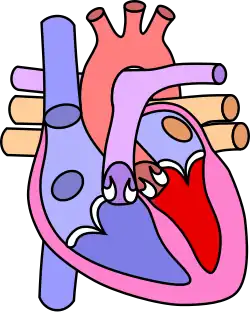

Четыре анатомических компонента:

- Вентрикулосептальный дефект — дефект межжелудочковой перегородки (ДМЖП) — соединяет между собой правые и левые отделы сердца. ДМЖП при тетраде Фалло всегда большой и нерестриктивный. Как правило, это перимембранозный ДМЖП (англ. perimembranous VSD), мышечный ДМЖП (англ. muscular VSD), или юкстаартериальный (околоартериальный; лат. juxta — около, подле, рядом) ДМЖП (англ. juxtaarterial VSD).

- Обструкция исходящего отдела правого желудочка — происходит за счёт одной из перечисленных или комбинации анатомических компонентов. К ним относятся инфундибулярный (подклапанный) стеноз исходящего отдела правого желудочка, клапанный стеноз лёгочной артерии, обструкция за счёт гипертрофированного миокарда правого желудочка, гипоплазия ствола и/или ветвей лёгочной артерии [6].

- Декстропозиция аорты — аорта отходит частично от правого желудочка или кровоток в ней поддерживается доминантно за счёт работы левого желудочка.

- Гипертрофия правого желудочка сердца — гипертрофия мышечного компонента правого желудочка развивается с возрастом.